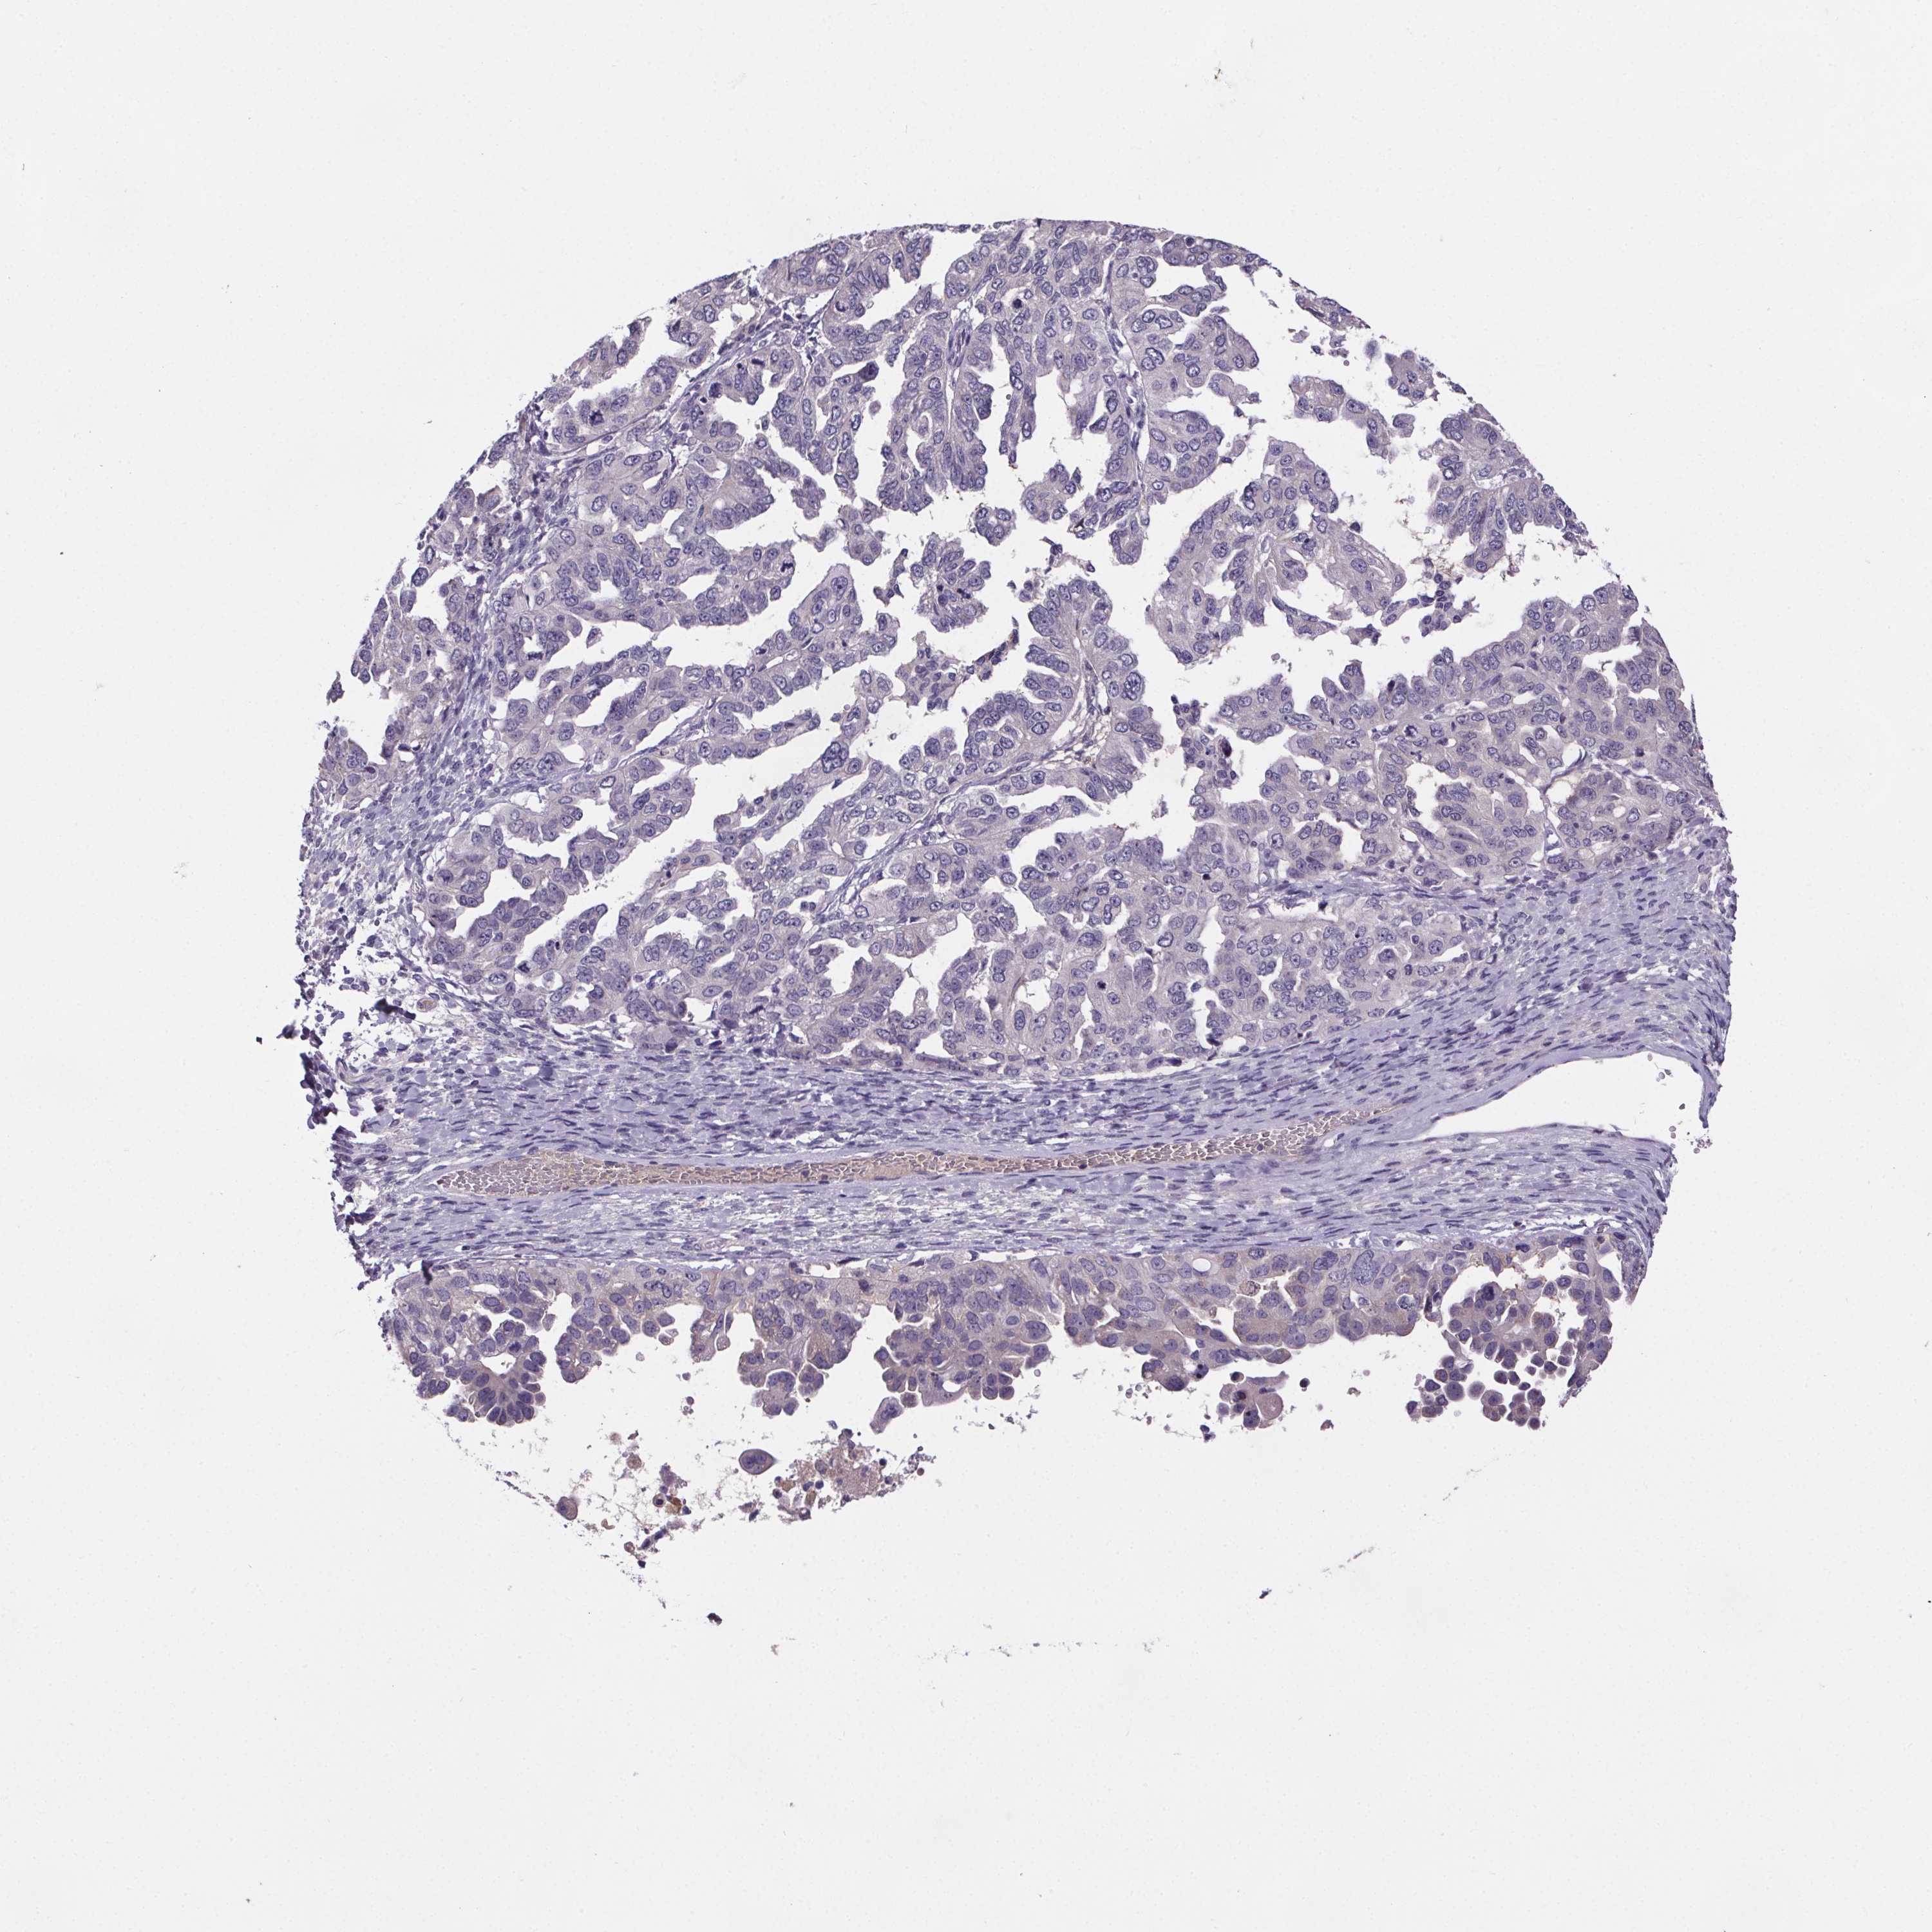

OVARIAN CANCER - Protein expressioni

A mouse-over function shows sample information and annotation data. Click on an image to view it in a full screen mode. Samples can be filtered based on level of antibody staining by selecting one or several of the following categories: high, medium, low and not detected. The assay and annotation is described here.

Note that samples used for immunohistochemistry by the Human Protein Atlas do not correspond to samples in the TCGA dataset.

Antibody stainingi

Antibody staining in the annotated cell types in the current human tissue is reported as not detected, low, medium, or high, based on conventional immunohistochemistry profiling in selected tissues. This score is based on the combination of the staining intensity and fraction of stained cells.

Each image is clickable and will lead to virtual microscopy that enables deeper exploration of all samples and also displays staining intensity scores, fraction scores and subcellular localization as well as patient and tissue information for each sample.

Antibody HPA004133

Antibody HPA043854

Cystadenocarcinoma, serous, NOS

Cystadenocarcinoma, mucinous, NOS

Carcinoma, endometroid